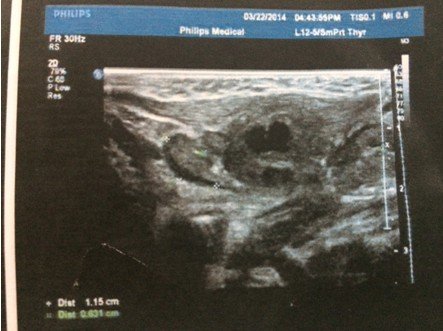

4个月大的婴儿,右颈部耳垂下方(2公分左右)有个硬疙瘩,婴儿无明显异常,吃奶睡觉等等一切正常,精神 状态很好,挂了3天的消炎水,图片为在2家医院做的B超,求解这个疙瘩是什么,需要怎么样治疗。医生叫继续挂消炎水进一步观察!(备注:B超2描述是:右侧颈部肌层后方探及22*15mm不均质低回声包块,其周围可见数枚低回声结节。 超声印象:右颈部包块伴周围淋巴结肿大。) 点击展开 匿名用户 2014-03-24 19:47 为您推荐: 其他回答 病情分析: 这个情况考虑是属于增生的症状, 指导意见: 你好,目前这个问题我建议及时消炎治疗,继续观察吧。 白其雨_6xwx 2014-03-24 21:36 相关问题 大夫您好我脖子右侧耳垂下方6公分左右 十五个月的宝宝耳垂前边脸颊上长了个长了个小疙瘩是怎么回事 十五个月的宝宝耳垂前边脸颊上长了个长了个小疙瘩是怎么回事

状态很好,挂了3天的消炎水,图片为在2家医院做的B超,求解这个疙瘩是什么,需要怎么样治疗。医生叫继续挂消炎水进一步观察!(备注:B超2描述是:右侧颈部肌层后方探及22*15mm不均质低回声包块,其周围可见数枚低回声结节。 超声印象:右颈部包块伴周围淋巴结肿大。)